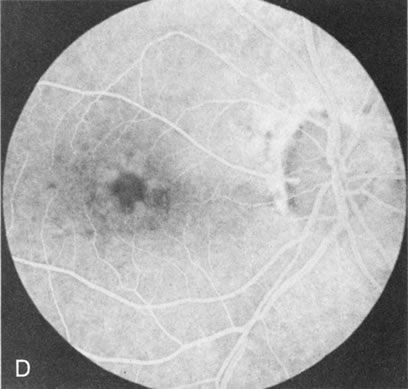

Fig. 1. Retinitis pigmentosa. A. A typical area of bone spicule pigmentation. B. Diffuse dye leakage is apparent throughout the posterior pole. C. The early angiogram shows dilated and irregular retinal radial peripapillary capillaries and perifoveal retinal capillaries. D. Leakage from these vessels are evident in the late angiogram.

Of more clinical importance is the role of FA in the diagnosis and treatment of cystoid macular edema (CME) (Fig. 1C and D). Stereoscopic FA indicates that the leakage, which may be diffuse or have the typical petaloid stellate appearance of CME, can come from the perifoveal retinal capillaries, from the choroid through the RPE, or from a combination of both sources.4 With the recent suggestion that CME in RP may be successfully treated with acetazolamide,5, 6 FA is thus important to document the diagnosis of CME, establish the origin(s) of leakage, and follow patients during and after therapy.